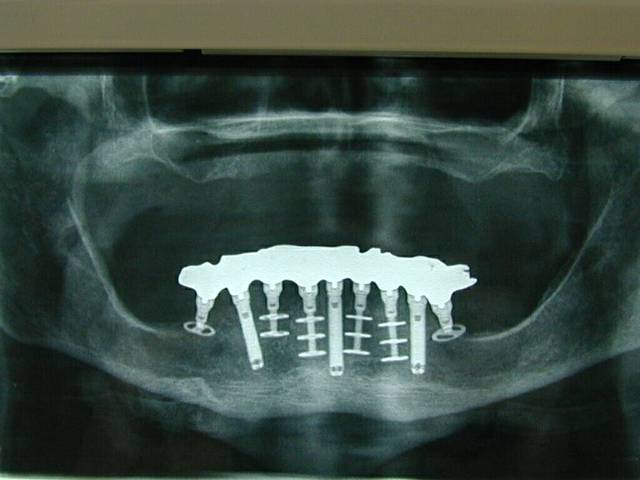

Tu veux des diskimplants, tu auras des diskimplants. Voila un cas fait il y a 5 ou 6 ans, avec de l'os trés mou (du D3 devant c'est pas courant)

Before bsmo9c - Eugenol

After zlsios - Eugenol

Me suis trompé le cas date de 98, et la pano a 2 ans.

Pour curieux impécunieux s'abstenir, les 35 et 45 répondent aux critères définissant l'ostéointégration, désolé! Quant à "pas d'os en mésial", le truc ovale noir que tu vois sous l'implant, c'est un machin que l'on appelle le trou mentonnier, t'inquiètes pas.

Panacher pourquoi pas: tu as un appui trabéculaire et cortical. Maintenant tu en auras certains qui sont pour et d'autres contre: il y a plusieurs théories de la basale.